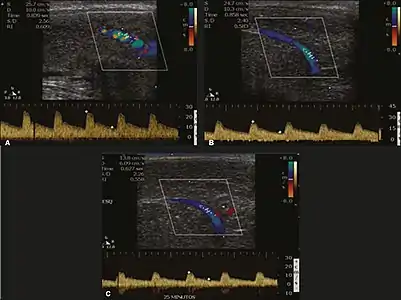

Erection can be induced by injecting 10–20 µg of prostaglandin E1, with evaluations of the arterial flow every five minutes for 25–30 min (see image). The use of prostaglandin E1 is contraindicated in patients with predisposition to priapism (e.g., those with sickle cell anemia), anatomical deformity of the penis, or penile implants. Phentolamine (2 mg) is often added. Visual and tactile stimulation produces better results. Some authors recommend the use of sildenafil by mouth to replace the injectable drugs in cases of contraindications, although the efficacy of such medication is controversial.[22]

Before the injection of the chosen drug, the flow pattern is monophasic, with low systolic velocities and an absence of diastolic flow. After injection, systolic and diastolic peak velocities should increase, decreasing progressively with vein occlusion and becoming negative when the penis becomes rigid (see image below). The reference values vary across studies, ranging from > 25 cm/s to > 35 cm/s. Values above 35 cm/s indicate the absence of arterial disease, values below 25 cm/s indicate arterial insufficiency, and values of 25–35 cm/s are indeterminate because they are less specific (see image below). The data obtained should be correlated with the degree of erection observed. If the peak systolic velocities are normal, the final diastolic velocities should be evaluated, those above 5 cm/s being associated with venogenic ED.[22]

Graphs representing the color Doppler spectrum of the flow pattern of the cavernous arteries during the erection phases. A: Single-phase flow with minimal or absent diastole when the penis is flaccid. B: Increased systolic flow and reverse diastole 25 min after injection of prostaglandin.[22]

Longitudinal, ventral ultrasound of the penis, with pulsed mode and color Doppler. Flow of the cavernous arteries at 5, 15, and 25 min after prostaglandin injection (A, B, and C, respectively). The cavernous artery flow remains below the expected levels (at least 25–35 cm/s), which indicates ED due to arterial insufficiency.[22]